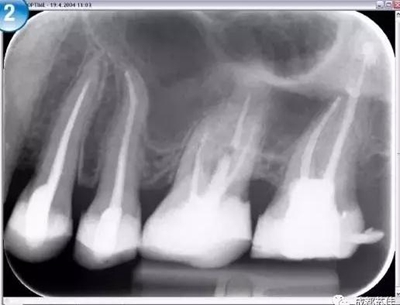

空間分辨率最高可達(dá)16.7lp/mm,16位(65,636)的灰度,能夠可靠的分辨出D1級(jí)別的齲損及細(xì)小至ISO 06 級(jí)別的根管器械。